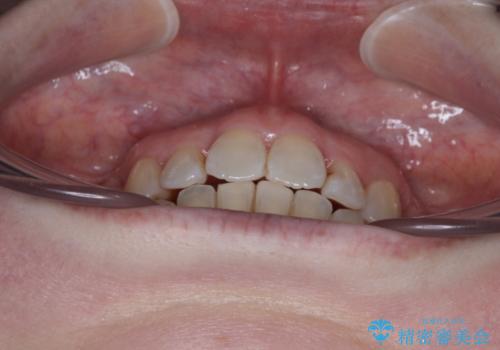

- 上下前歯のデコボコと、上顎の八重歯を気にして来院された患者様です。

下顎に対して上顎が前方にあり、第一大臼歯による咬合状態は上顎前突であったため、上顎のみ左右の第一小臼歯を抜歯し、ワイヤー装置にて矯正治療を行うこととしました。